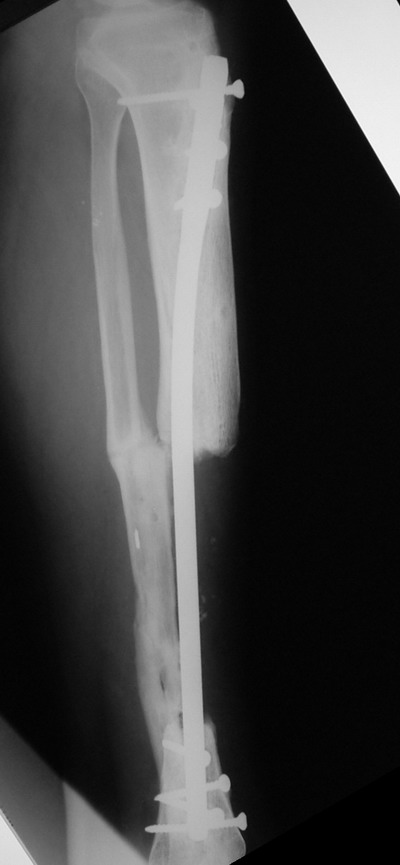

> Пациент Г.,мужчина 56 лет, Хронический посттравматический остеомиелит

> костей левой голени. *Свищевая форма( Свищ в обдасти дистального

> фрагмента по передней поверхности).* Латентное течение. Дефект

> большеберцовой кости в с/з 8 см....

Владимир, свободная костная пластика на фоне свища вряд ли оправдана. Почему

не рассматриваете вариант транспорта кости по Илизарову? Что собираетесь

антибиотиками, бусах. После купирования инфекции переходить к замещению

дефекта: за счет удлинения концов б\б кости или тибиализации м\б. На

начальном этапе фиксация только в аппарате, в последствие для удержания

достигнутого можно перейти на фиксацию интрамедуллярным штифтом (см.

вложенные файлы)